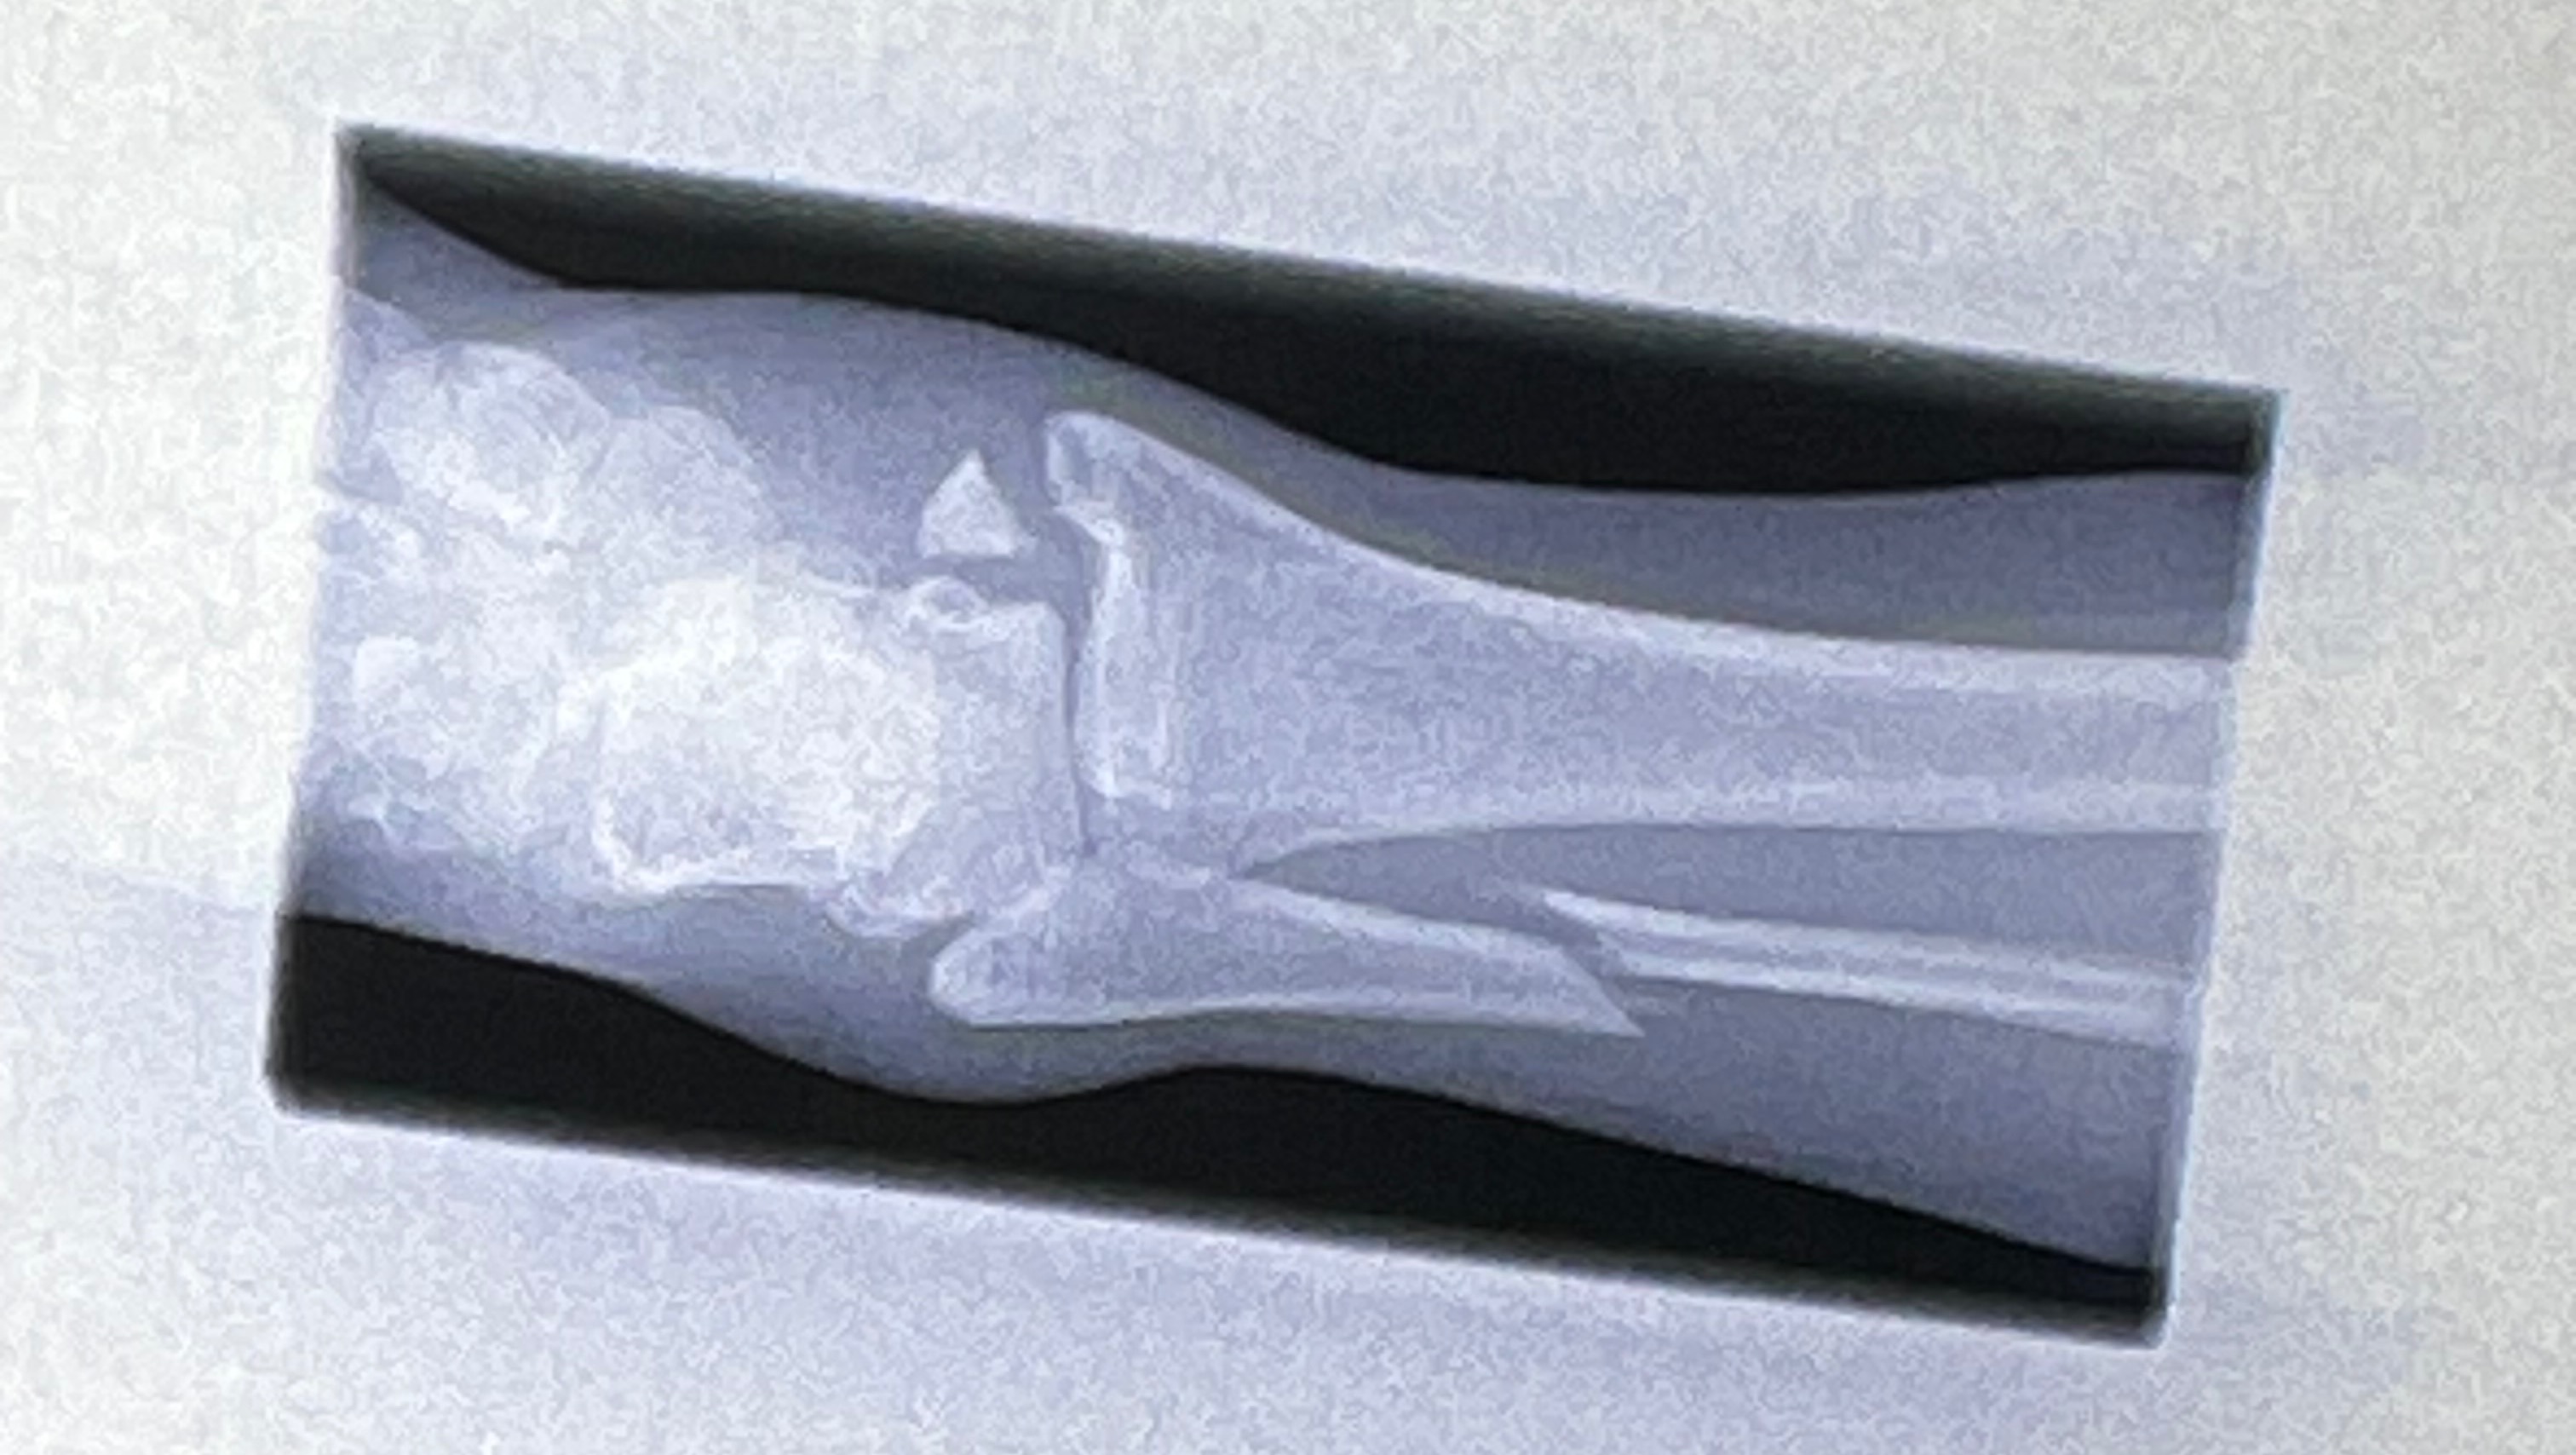

Hi, I’m Natalie and I recently broke my ankle quite severely while competing in what was supposed to be a “friendly” Judo competition. I have a trimalleolar fracture, which means my ankle is broken in 3 places and I will need surgery. I also have extensive tendon and ligament damage.